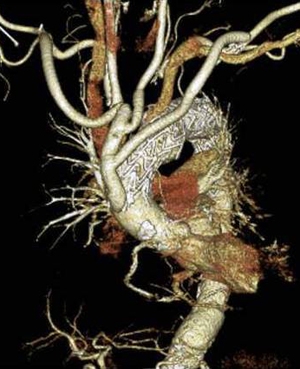

頸部分枝の再建をしてステントグラフトを上行大動脈から下行大動脈まで挿入した(ハイブリッド手術後)

手術後(ステントグラフト治療)